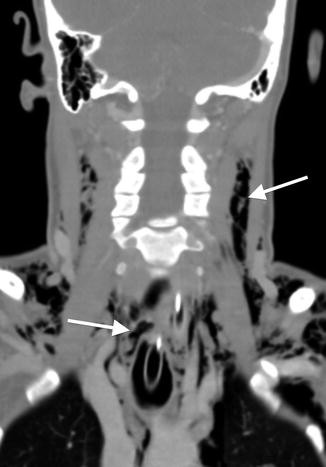

Coronal image from a CT angiogram demonstrates extensive soft tissue emphysema throughout the superficial and deep soft tissues of the neck (arrows) in a patient with a history of benzodiazepine overdose who was intubated in the field